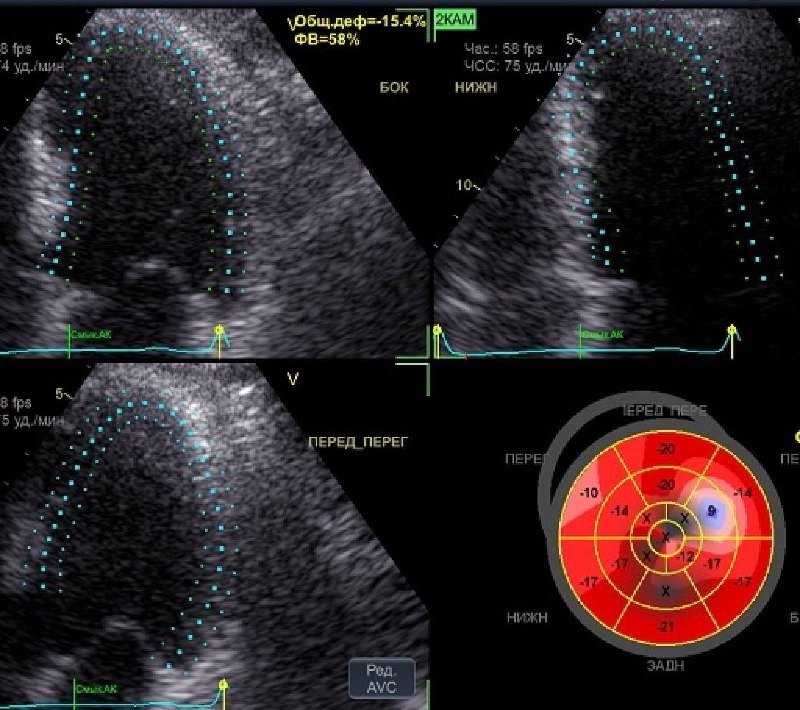

Возможно вы пропустили нашу главную новость прошлого года 😉 Идет второй год, как мы открыли новое направление: ЭХО-КС в формате AFI 3.0 😊 Через пару лет без этой технологии УЗИ сердца делать не будут 😉 Сегодня я с белой завистью смотрю на современный ультразвук в кардиологии и думаю, не уйти ли в ЭХО-КС ❤️ Клиника САРЕНКО - это всегда только передовые технологии 🤝 Спасибо, что доверяете нам 🫶 😍 Здесь несколько фото и видео моего сердца и наших постоянных пациентов. ✅ Наш Vivid T9 упрощает работу врача в рутинных измерениях, автоматизирует процесс оформления протокола и дает больше времени для непосредственной работы с пациентом. #саренко

😉 Идет второй год, как мы открыли новое направление: ЭХО-КС в формате AFI 3.0

😍 Здесь несколько фото и видео моего сердца и наших постоянных пациентов.

✅ Наш Vivid T9 упрощает работу врача в рутинных измерениях, автоматизирует процесс оформления протокола и дает больше времени для непосредственной работы с пациентом.